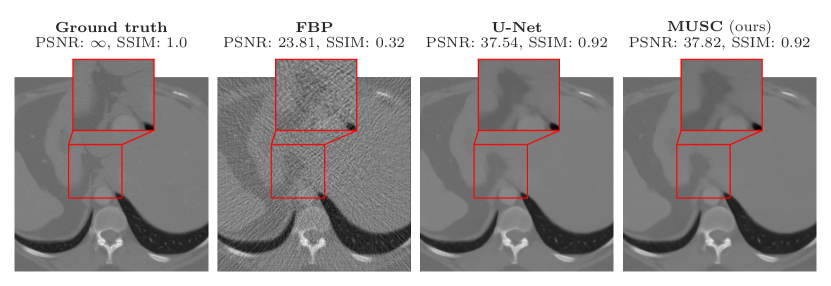

IV-B CT reconstruction

Computed tomography (CT) aims to recover images from their sparse-view sinograms. We use the LoDoPaB-CT dataset [64] to benchmark our results. This dataset contains more than 40000 pairs of human chest CT images and their simulated low photon count measurements. The ground truth images of this dataset are human chest CT scans corresponding to the LIDC/IDRI dataset [66], cropped to 362 × 362 pixels. The low-dose projections are simulated using the default setting of [64].

We compare the reconstruction performance of MUSCs with five modern CNN baselines, namely CINN [67], U-Net++ [68], MS-D-CNN [69], U-Net [31], and LoDoPaB U-Net [64]; the LoDoPaB U-Net refers to a modified U-Net architecture tailored to the LoDoPaB-CT task. Figure 3 shows the reconstruction results of a test sample. In Table III, we quantitatively compare MUSC with two classic methods (FBP and TV) together with five CNN baseline methods mentioned above. As shown in Table III, MUSC outperforms all baselines. The metrics PSNR and PSNR-FR are taken from [49]: For a ground-truth signal and its approximation , we define